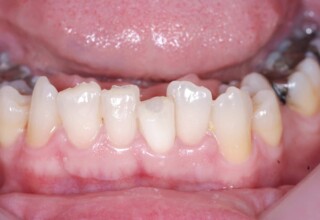

Οι όψεις ρητίνης προσφέρουν έναν οικονομικό τρόπο αισθητικής βελτίωσης της εμφάνισης των προσθίων δοντιών ενίοτε και των προγομφίων. Οι δυνατότητες τους πολλές, μπορούν να κάνουν και θαύματα! Ο μονός περιορισμός η κλινική ευχέρεια και η φαντασία του επεμβαίνοντος. Σε αυτήν την ασθενή οι τέσσερεις άνω τομείς είχαν ο καθένας το δικό του πρόβλημα(δυσχρωμία, απόκλιση) και επιπλέον: διαστήματα, πολλαπλές αποχρώσεις, κακή σχέση μεταξύ τους και με τα ούλα. Αποκαταστάθηκαν με τέσσερεις άμεσες όψεις ρητίνης (η μια πάνω σε στεφάνη πορσελάνης εμφυτεύματος!!!) οι οποίες κατασκευάστηκαν ενδοστοματικά!